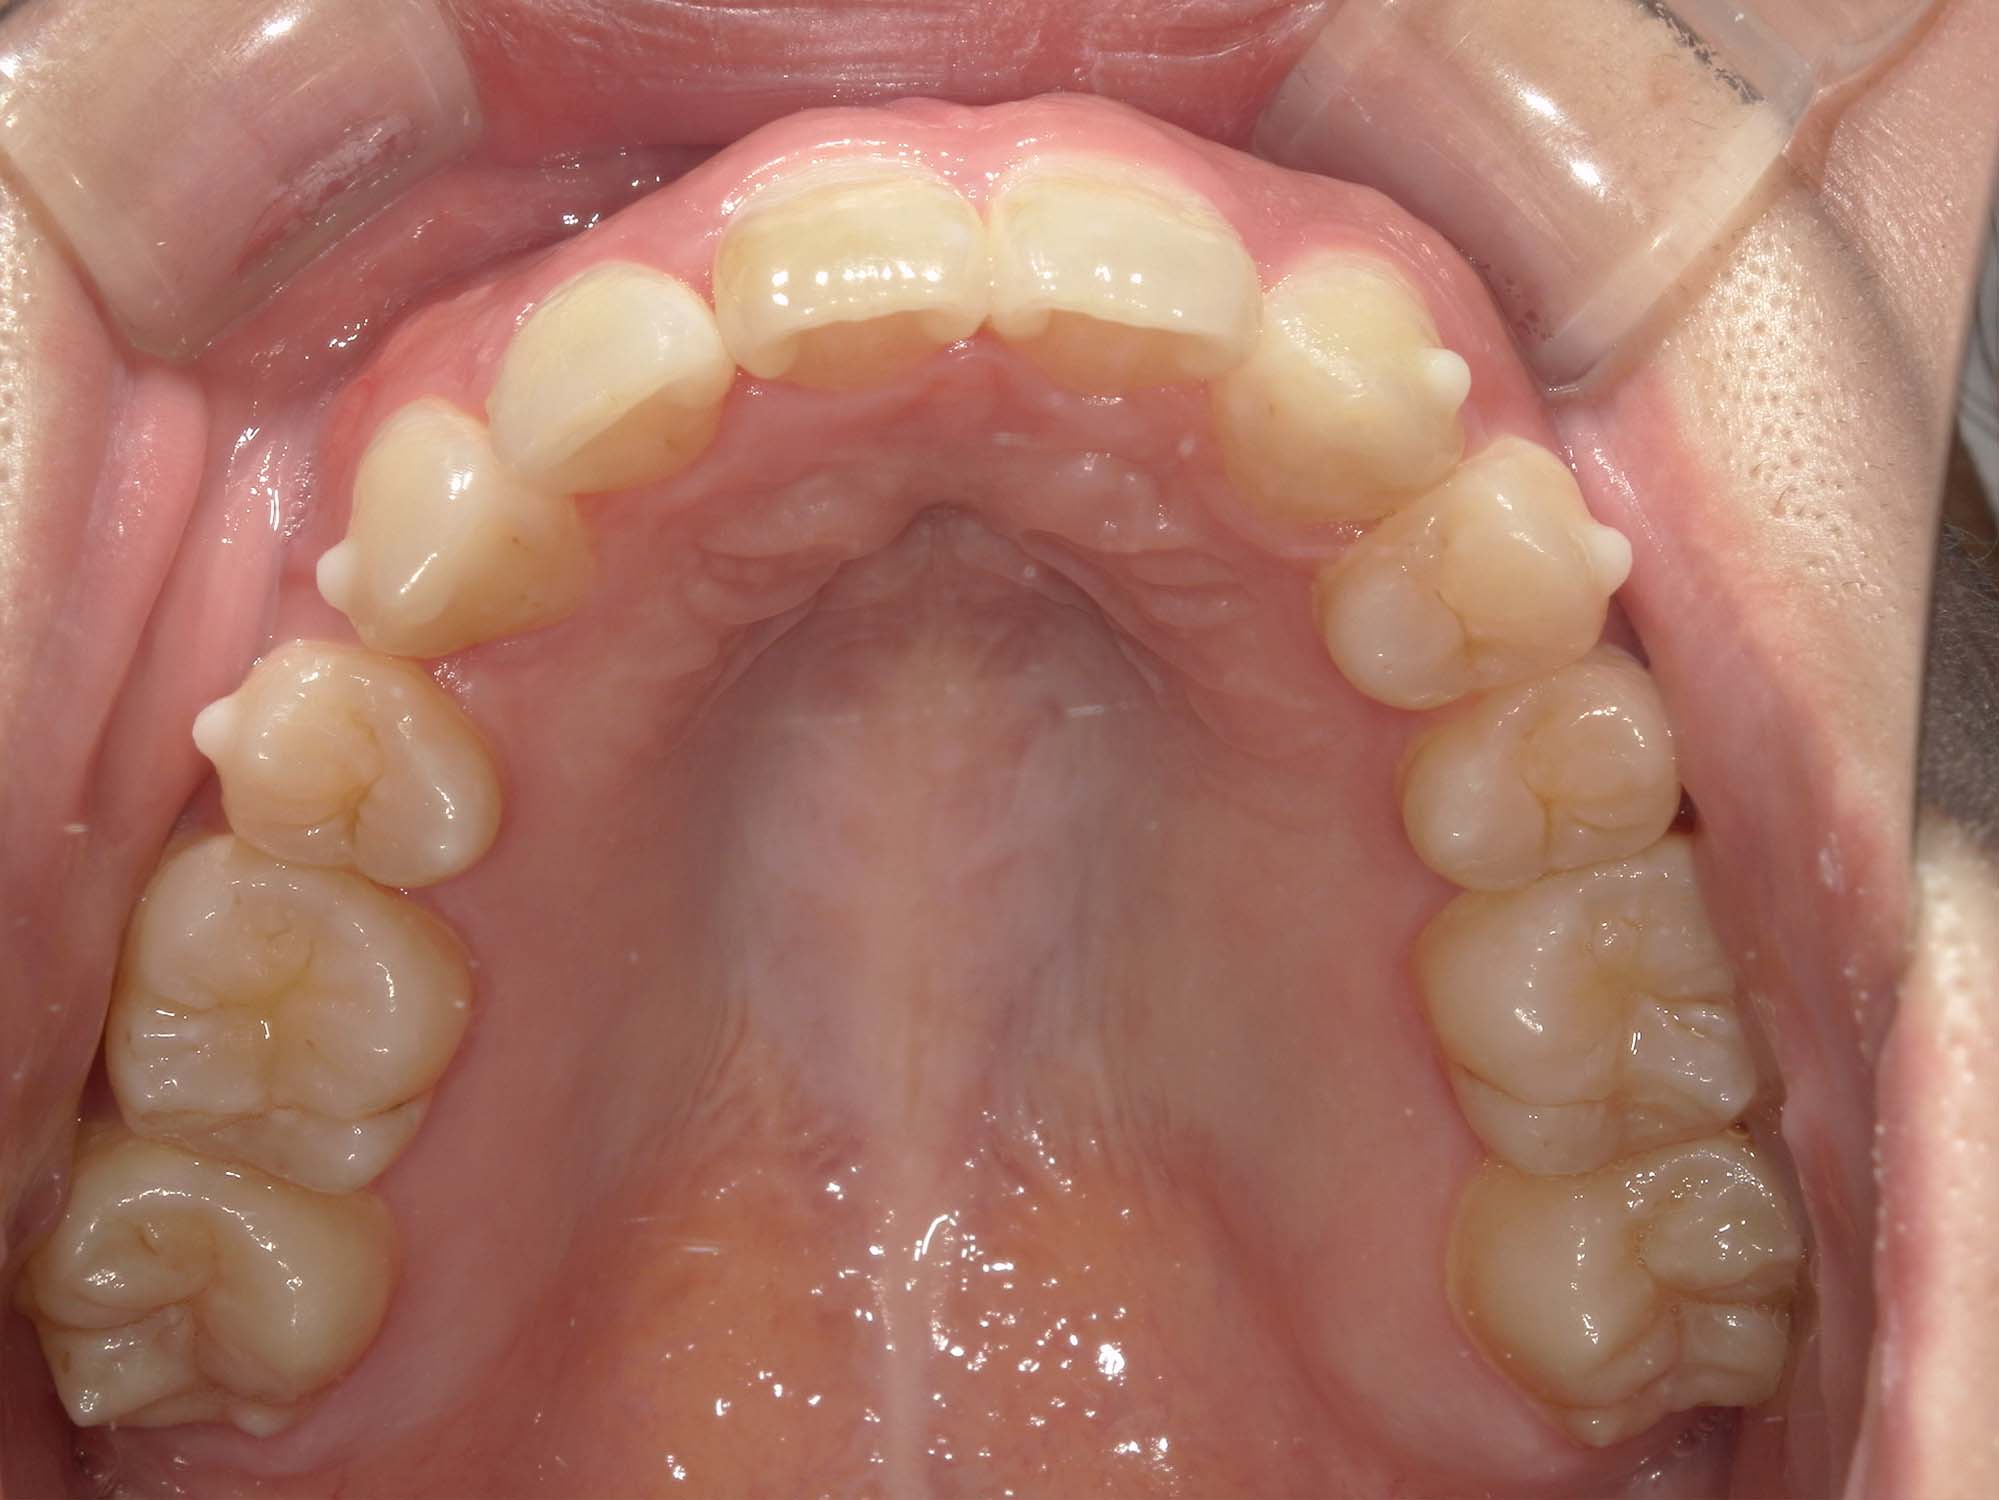

| 年齢・性別 | – |

|---|---|

| 主訴 | 叢生が気になる |

| 治療期間・回数 | 1年9ヶ月 |

| 費用 | 1,011,000円 |